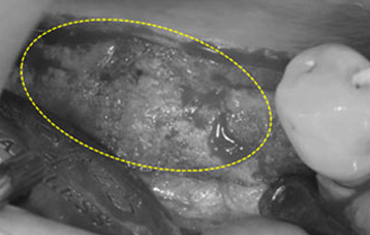

치료 후윗턱뼈 공기주머니에 뼈이식

치료 전

치료 후